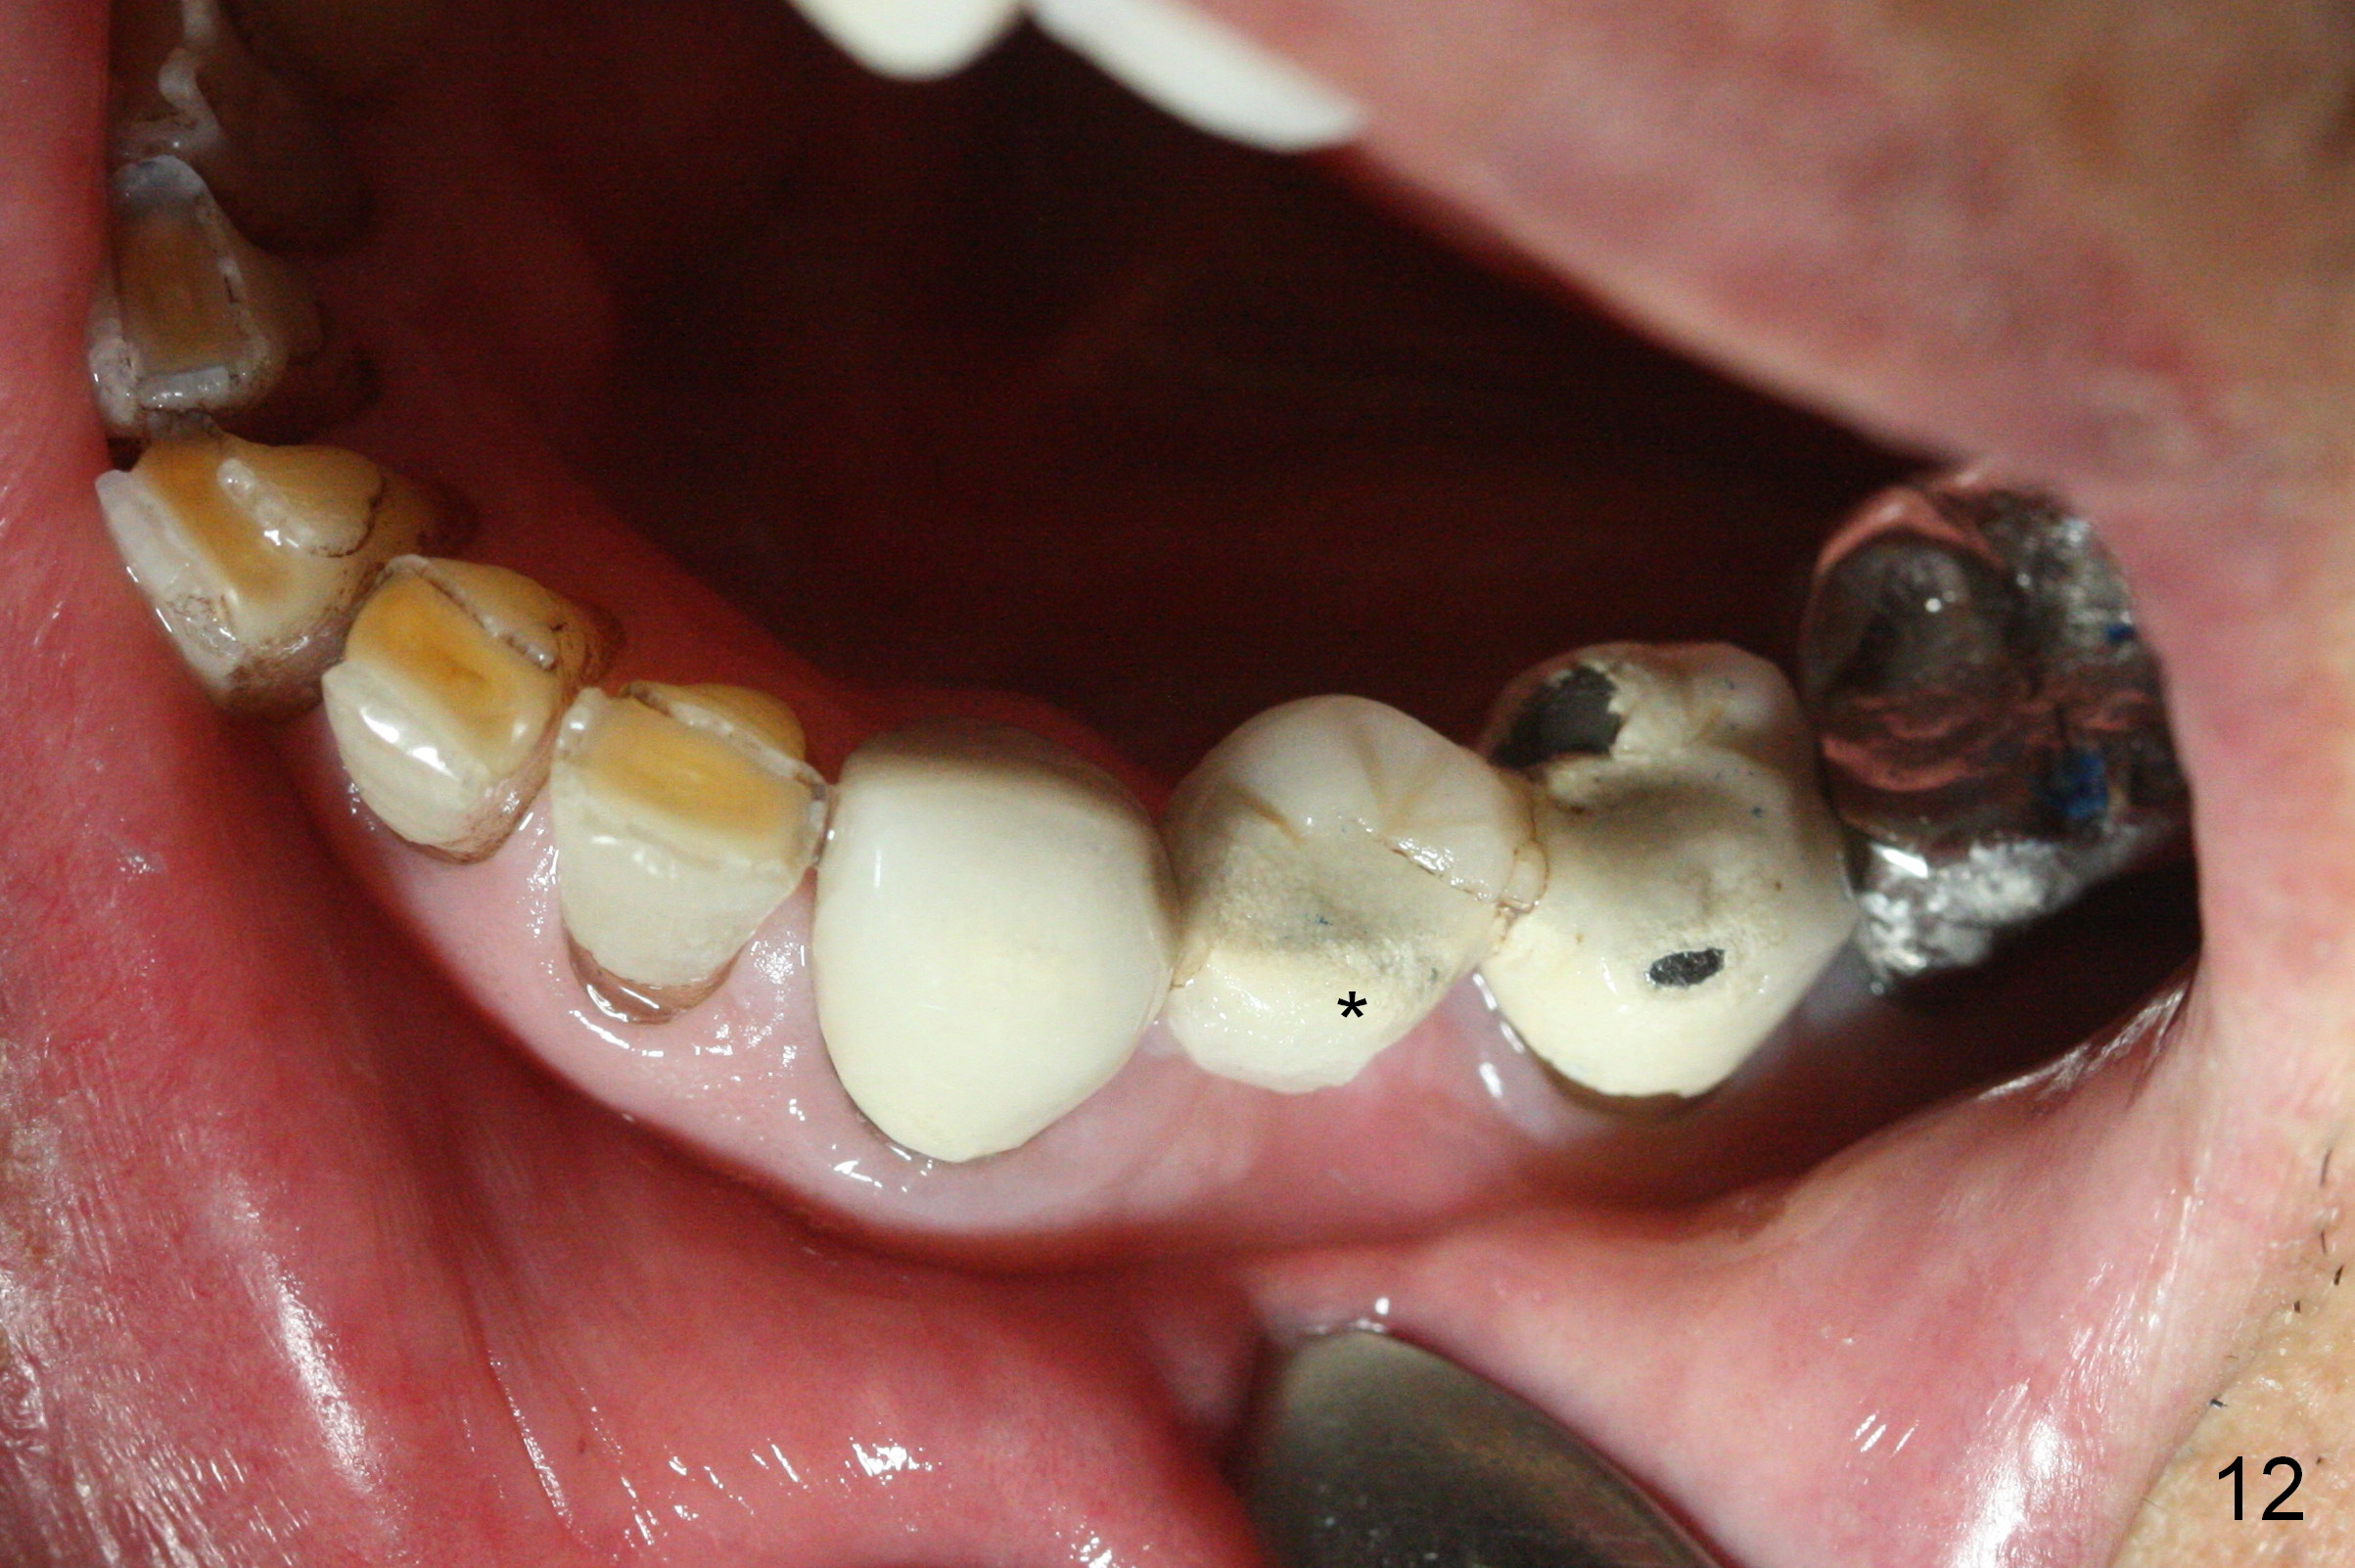

The fistula buccal to #14 remains 1 week postop (Fig.7) and disappears 1 months postop. The fistula does not re-appears 3 months postop with the implants at #13,15 apparently osteointegrated (Fig.8). With relining #13-15 provisional with increased vertical height (Fig.11), the patient has bilateral posterior contact (Fig.9), while the lower incisors do not contact the cinguli of the upper incisors (Fig.10 *). The space between the tooth #12 and the pontic #21 is unfavorable for posterior occlusal stability (Fig.11 *). Porcelain is chipped off the buccal surface of the pontic (Fig.12 *). If the patient does not afford an implant at #21 with redo crowns at #20 and 22 (Fig.13), what else could be done? He will return for #15 implant placement 4 months post socket preservation.